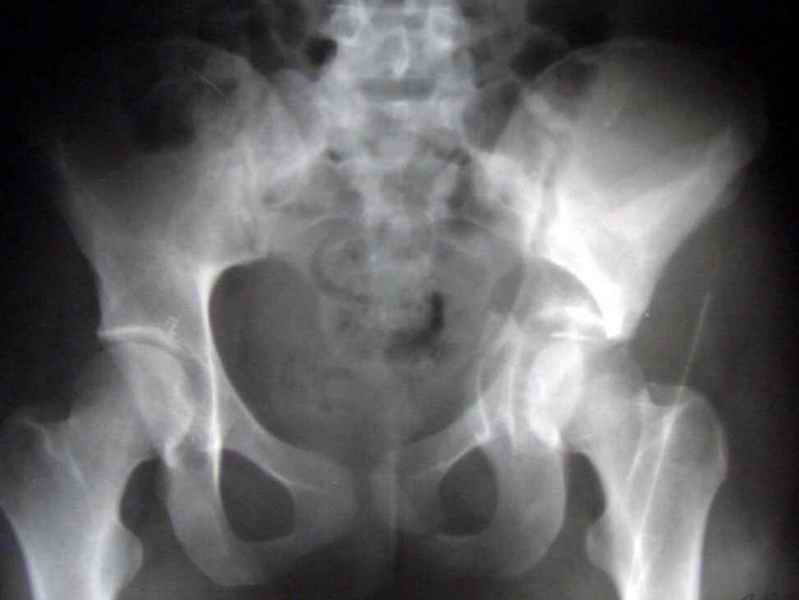

Посылаю схемы и 3D реконструкцию подобного повреждения. Называется он полным высоким двухколонным переломом вертлужной впадины, а "переломы крыла и тела подвздошной кости" входят в это понятие.

Вариантов остеосинтеза много (можно и не оперировть, т.к. конгруентность при таких переломах как правило сохраняется)

прикладываю схему доступа и случай.